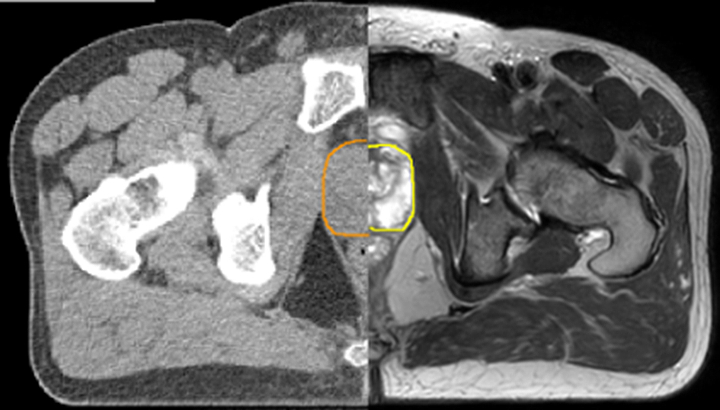

With its exceptional soft-tissue visualization capabilities and wide range of image contrasts, MRI has become a powerful tool to help more precisely define tumor boundaries. This is particularly important as it has been established that there is a high degree of uncertainty in target volume delineation, and it is even reported to represent the largest uncertainty in the entire radiotherapy process for most tumor sites**. Better visualization of the target area and nearby organs-at-risk is a key factor in enhancing target volume delineation. MRI’s expanding role also can be attributed to its functional imaging capabilities, which can inform both target characterization and treatment response.

With its superior soft tissue contrast compared to CT, MRI offers exquisite visualization of tumor boundaries and proximity to nearby critical structures.

The ability to tune contrasts can provide even more valuable information about tumor characteristics and tumor extent to facilitate enhanced delineation, and also provides possibilities for dose boosting strategies.

Diffusion-weighted imaging (DWI) for example depicts areas of high signal intensity in soft tissues that are indicative of the restricted water mobility (i.e., diffusion) of a tumor and can also be used to identify lymph nodes. Changes in the tissue’s or lesion’s apparent diffusion coefficient (ADC) can provide insights that help predict the tumor’s response to radiotherapy.